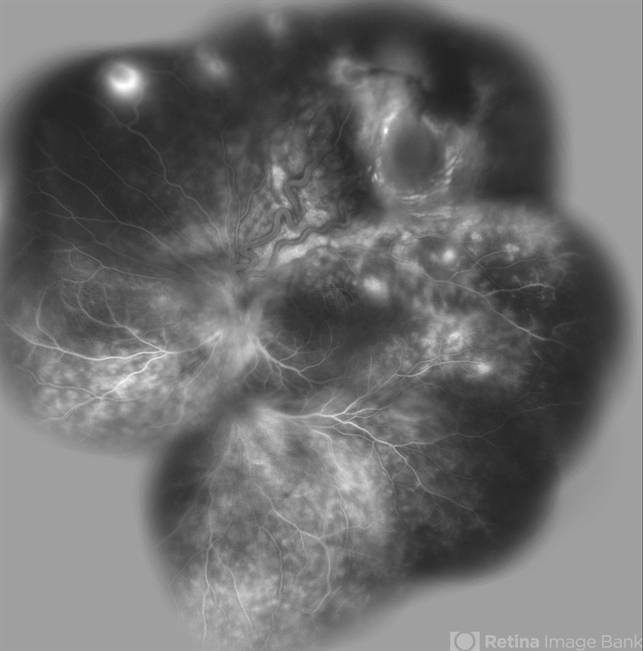

- Von Hippel-Lindau, exudative retinal detachment, retinal angiomatous proliferation (RAP)

- Wide field FA image of the left eye of a 25-year-old woman with exudative retinal detachment secondary to retinal angiomatosis (Von Hippel-Lindau).